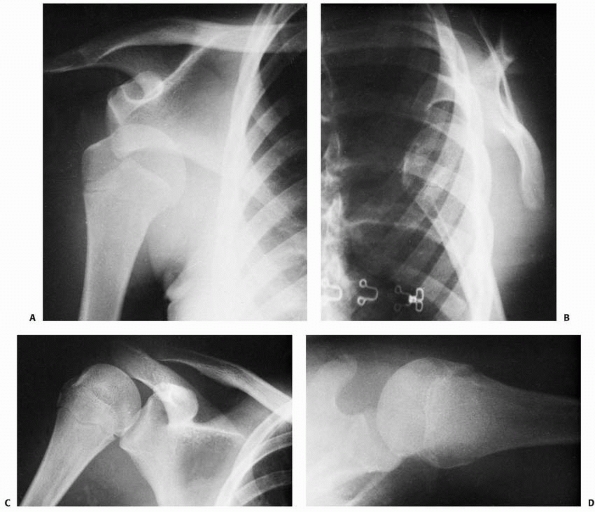

Distal clavicular fractures lateral to the coracoclavicular ligament

and injuries to the AC joint are categorized by a system proposed by

Dameron and Rockwood

(Fig. 17-6).125

Although derived from the system for adult distal clavicular injuries,

this classification system incorporates the observation that the distal

clavicle displaces through a disruption in its periosteal sleeve rather

than by true disruption of the coracoclavicular ligaments. Also, true

AC dislocations rarely occur in children. Most injuries in this region

are either metaphyseal or physeal fractures.159,420

However, because distal clavicular epiphyseal ossification does not

occur until age 18 or 19, these injuries may have the radiographic

appearance of an AC dislocation rather than a fracture

(pseudodislocation).159,420,543

are characterized by mild strains of the ligaments or periosteal tears.

No gross changes are seen on radiographs. Type II injury includes

complete disruption of the AC ligaments or lateral periosteal

attachment, with mild damage to the superolateral aspect of the

periosteal sleeve. Mild instability of the distal clavicle results from

this type of injury, and minimal widening of the AC joint may be seen

on a radiograph. In type III injury, complete disruption of the AC

ligaments or periosteal attachment occurs in addition to a large

disruption in the superolateral periosteal sleeve. Noticeable superior

displacement of the distal clavicle is seen on an AP radiograph, and

the coracoid-clavicle interval is 25% to 100% greater than on the

contralateral uninjured side.73,126

Similar soft tissue disruptions are seen in type IV injuries. The

distal clavicle, however, is displaced posteriorly and is often

embedded in the trapezius muscle.31

Minimal changes may be noted on an AP radiograph, and an axillary

lateral radiograph may be required to identify the posterior clavicular

displacement. Type V injuries are similar to type III injuries; the

difference lies in the fact that the superior aspect of the periosteal

sleeve is completely disrupted in type V injuries. This allows

displacement of the distal clavicle into the subcutaneous tissues,

occasionally splitting the deltoid and the trapezius muscles. On an AP

radiograph, the coracoid-clavicle interval is more than 100% greater

than on the contralateral uninjured side. In type VI injuries, the

distal clavicle is displaced inferiorly, with its distal end located

inferior to the coracoid process.188